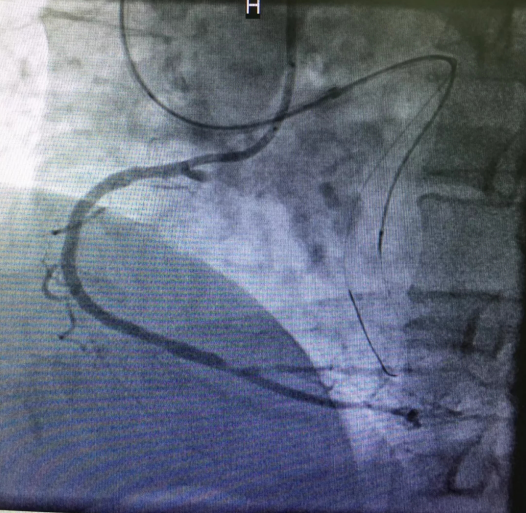

心内三完成我院首例逆向开通冠脉CTO病变